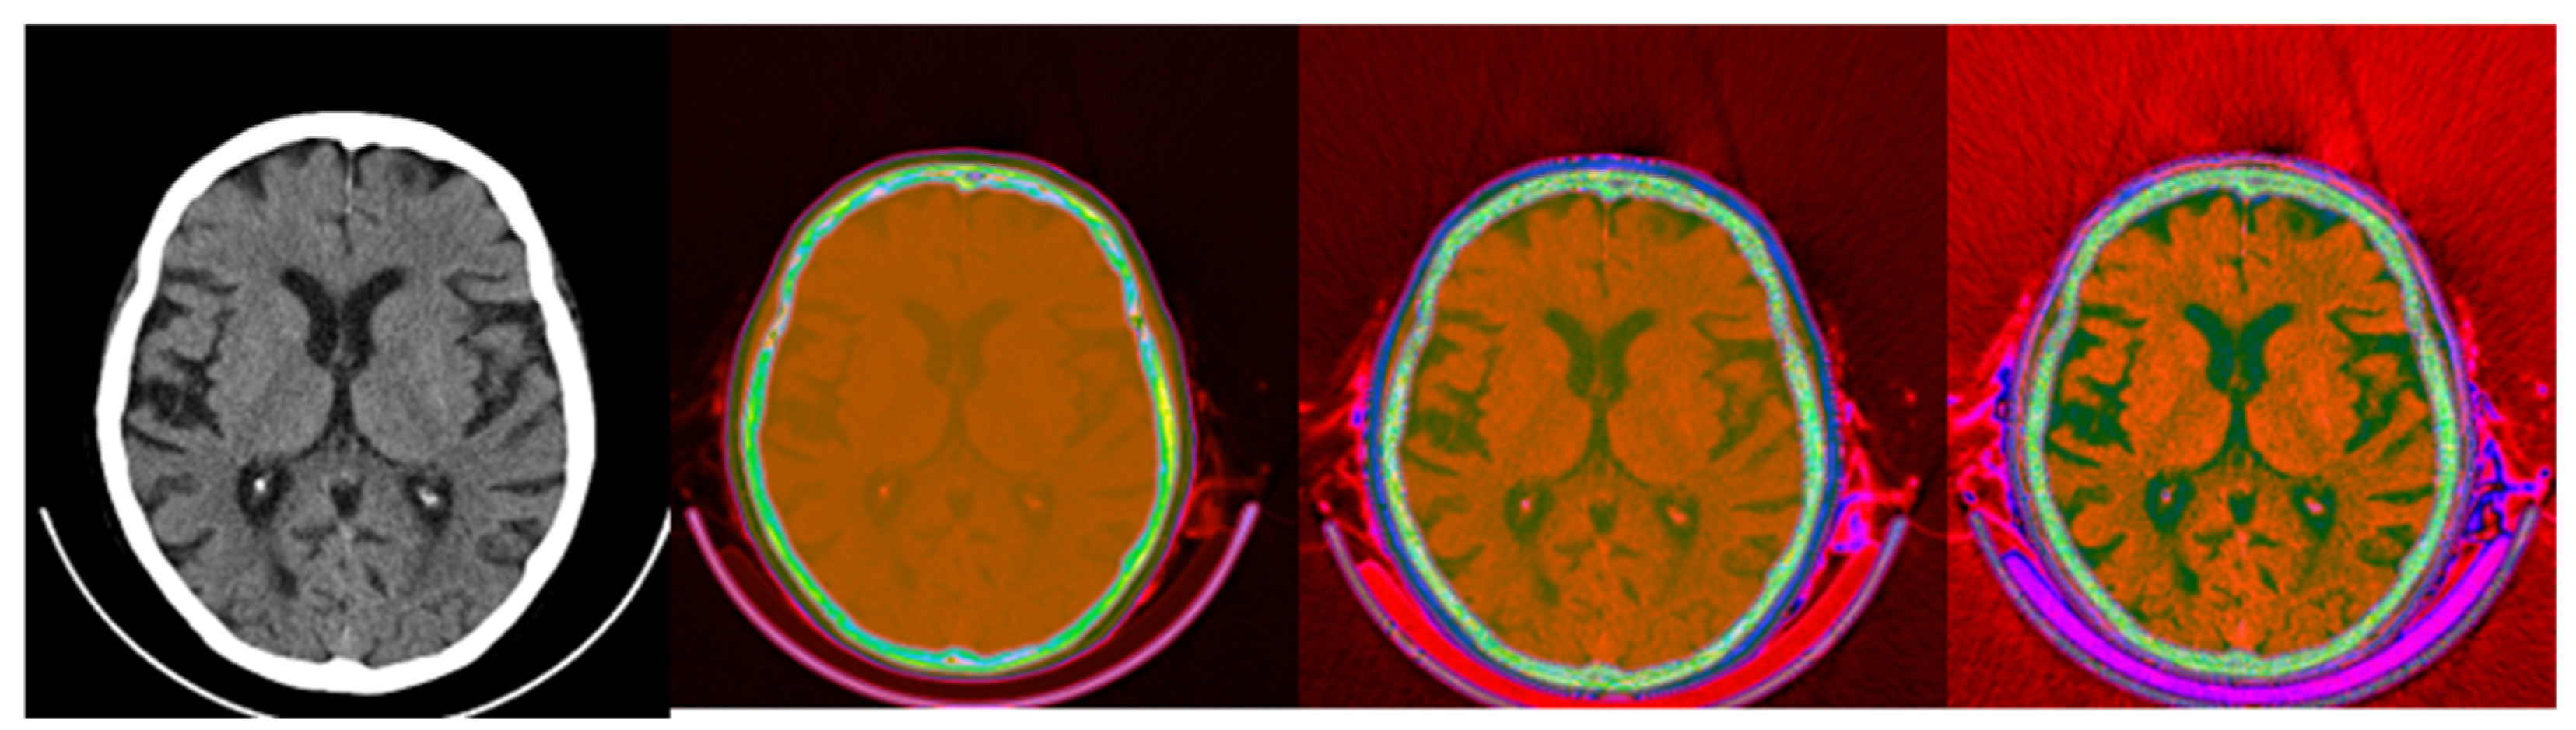

3.2. Colormap Folding Application

4. Discussion